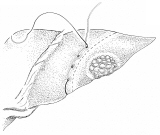

胃全摘術後の再建

器械吻合器を用いた、横行結腸間置法。術後しばらくは、オ(クビ;ナラ)判別困難だった由。